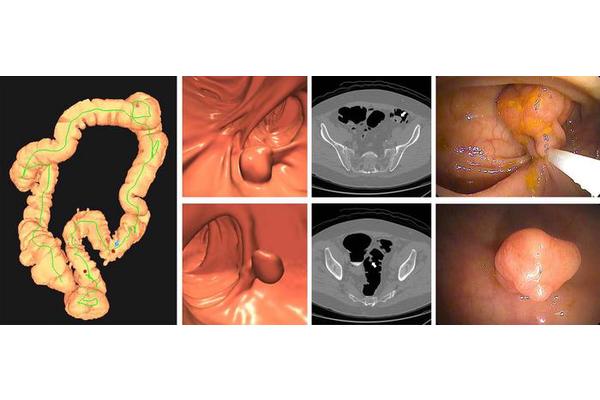

Home Science News Biology New Study Reveals Striking Parallels Between Atherosclerosis and Tumor Development June 17, 2025 in Biology Reading Time: 4 mins read 0 67 SHARES 606 VIEWS Share on